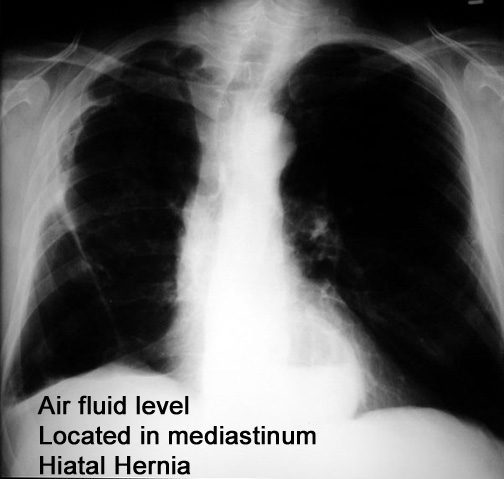

Case 6

Lateral

Labeled Image

What is the differential for air fluid levels in the mediastinum?